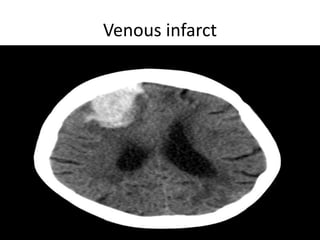

Venous infarct

• Venous infarcts.

Vascular Insults • SubarachniodHemorrhage. • Lobar and basal ganglia bleeds. • Ischemic strokes. • Venous infarcts. • Disections